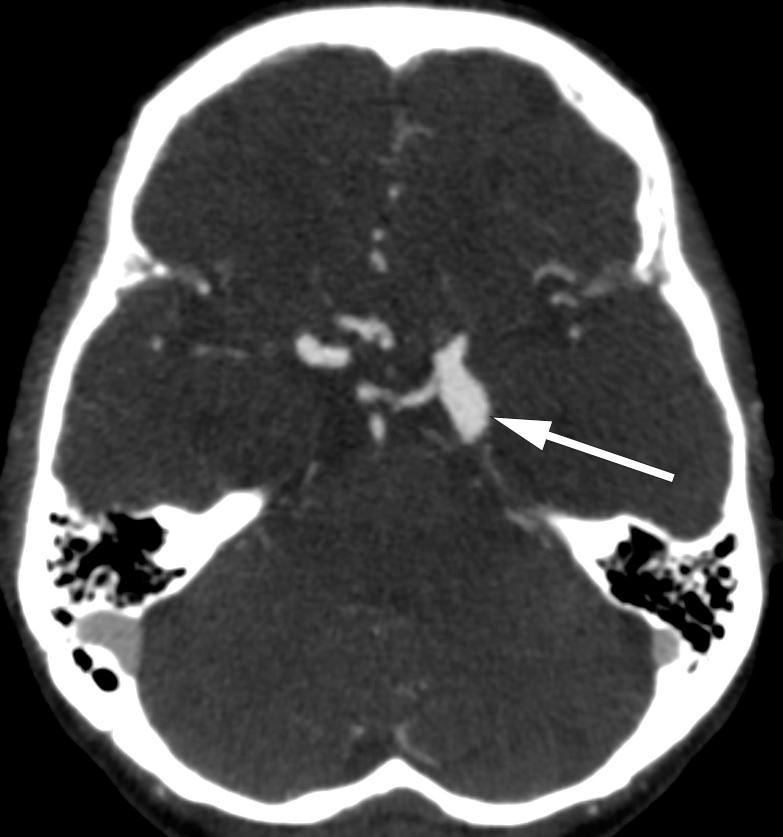

A CT scan of the head with angiography performed on admission showed growth of the aforementioned aneurysm to 15 x 9 mm. The neurosurgical department was contacted due to suspicion of imminent rupture, and urgent assessment was agreed for the following morning. However, the same evening the patient had hyperacute occipital headache with accompanying neck stiffness and hypertension, but no reduction in consciousness. CT scan of the head revealed a subarachnoid bleeding. The patient was immediately transferred to the department of neurosurgery where craniotomy and clip ligation of the ruptured aneurysm were performed. The patient survived but the neurological sequelae were severe.